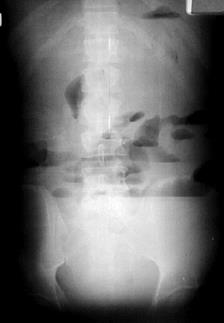

Острая непроходимость кишечника. Больной, у которого предполагается острая непроходимость кишечника, должен быть подвергнут срочному рентгенологическому исследованию. Ему следует произвести просвечивание и обзорный снимок брюшной полости при вертикальном положении тела и без применения контрастного вещества. Если состояние больного тяжелое, просвечивание и снимок производятся в горизонтальном положении на боку.

При любом виде острой непроходимости наблюдается вздутие кишечных петель и появление в них скоплений газа и жидкости. Источником метеоризма могут быть проглоченный воздух и газы крови, тогда как жидкое содержимое составляется пищеварительными соками и секретом кишечной стенки. Вздутые и растянутые петли кишок отчетливо вырисовываются на рентгенограммах; на фойе заключенного в кишках газа видны горизонтальные уровни жидкости (так называемые уровни, или чаши Клойбера). Эти рентгенологические признаки обнаруживаются уже через 1-2 часа после начала заболевания.

Когда диагноз кишечной непроходимости установлен, необходимо определить ее тип, т. е. провести дифференциацию между динамической и механической непроходимостью. Это сделать нетрудно. При динамической непроходимости вздуты все кишечные петли, по всех петлях содержится газ и жидкость. При механической непроходимости резко вздуты все петли, расположенные выше места закупорки или сдавления кишки, но находятся в спавшемся состоянии и не содержат газа и жидкости все петли дистальнее места закупорки. Последний признак позволяет не только распознать механическую непроходимость, но и определить ее уровень. Например, если на снимках определяется вздутие тонких кишок, а толстая кишка находится в спавшемся состоянии, можно с уверенностью установить непроходимость тонкой кишки.

Кроме того, при динамической непроходимости обращает на себя внимание постоянство рентгенологической картины, отсутствие перистальтических движений кишок. При механической непроходимости уровни жидкости все время меняют свое положение в связи с энергичными перистальтическими движениями, а на повторных снимках определяется изменение положения вздутых петель и уровней жидкости в них. В тех случаях, когда подозревается непроходимость толстой кишки, показано вливание в нее контрастной массы с помощью клизмы. Такое исследование позволяет не только подтвердить наличие непроходимости, но и определить ее причину, а в некоторых случаях способствовать восстановлению проходимости кишки (при завороте сигмовидной кишки, при инвагинации толстой кишки).